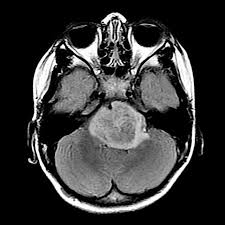

For example, if a brain tumor is located in the cerebellum at the back of the head, a child may have trouble with movement, walking, balance and coordination. This is partly because pressure in the brain increases when you're lying down, and a tumor can make that worse. Many children with a brain tumor experience headaches before their diagnosis. Tumors that spread from other places in the body generally have a worse prognosis, because the dog has much more cancer to deal with than just that in the brain. Some of the more common symptoms of a brain tumor in children include:

Brain Tumors In Children 8 Warning Signs You Should Know Johns Hopkins Medicine from www.hopkinsmedicine.org — written by ann pietrangelo — updated on june 25, 2018 general signs and symptoms In children, tumors usually start in a part of the brain that controls movement and coordination. Other signs of brain damage include: A tumor pressing on or encroaching on other parts of your brain and keeping them from working like they should. It is grows most often in the cerebellum. Most brain stem tumors can't be removed with surgery. Like clumsiness, losing feeling in a part of your body or face is something to keep an eye on, schwartz says. Plus, learn the signs of brain metastases.

For example, if a brain tumor is located in the cerebellum at the back of the head, a child may have trouble with movement, walking, balance and coordination. Brain tumor warning signs and symptoms you should know medically reviewed by seunggu han, m.d. There are many types of brain tumors and the treatment and outlook for each is different. Sometimes we can tell because the baby's liver is enlarged. Of course, it is not impossible to detect signs and symptoms of a brain tumor, and here we will explain some common signs you can have. I wish i didn't have experience in this matter, but unfortunately i do. If the tumor puts pressure on certain areas of the brain, it can affect how the body functions. A tumor pressing on or encroaching on other parts of your brain and keeping them from working like they should. If it is so difficult to decipher how the brain works, imagine trying to notice a brain tumor without seeing it. It's unusual, but it can happen. It can be tough to know what to say to a parent who is facing a child's health crisis. Plus, learn the signs of brain metastases. While brain cancer can limit where, when, and how you travel, getting away may be good for you.

A tumor pressing on or encroaching on other parts of your brain and keeping them from working like they should. Particularly if a tumor forms on the brain stem—the place where your brain connects with your spinal cord—you may experience loss of feeling or clumsy movements. This tumor is found in the brain stem. In children, tumors usually start in a part of the brain that controls movement and coordination. One red flag to watch out for: Other signs of brain damage include: Some of the symptoms for the most common cancers in infants are listed below. While brain cancer can limit where, when, and how you travel, getting away may be good for you. The signs and symptoms of a brain tumor vary greatly and depend on the brain tumor's size, location and rate of growth. However, if it lasts more than 14 days and you don't have a clear reason why, you should seek advice from your gp. Wait until you have all of the details. Brain tissue dysfunction caused by a growing tumor may cause other symptoms, depending on the tumor's location. Most importantly, no matter what symptoms your child has, tell your pediatrician if you are worried that your child could have cancer.

If the tumor puts pressure on certain areas of the brain, it can affect how the body functions. It can be tough to know what to say to a parent who is facing a child's health crisis. Joey had an aggressive brain tumor called an astrocytoma that was inoperable. Learn more about symptoms, diagnosis, and treatments. Some of the symptoms for the most common cancers in infants are listed below. Your child may have any of the following: This tumor is found in the brain stem. It can present with a tumor near or around the spine as well as in the abdomen or the adrenal gland. Some of the more common symptoms of a brain tumor in children include: Many children with a brain tumor experience headaches before their diagnosis. It might be that you do have a reason to be concerned, or your doctor might be able to reassure you that your child is not at risk, either with a good history and physical examination, or a few screening tests. If it is so difficult to decipher how the brain works, imagine trying to notice a brain tumor without seeing it. Changes in memory or thinking